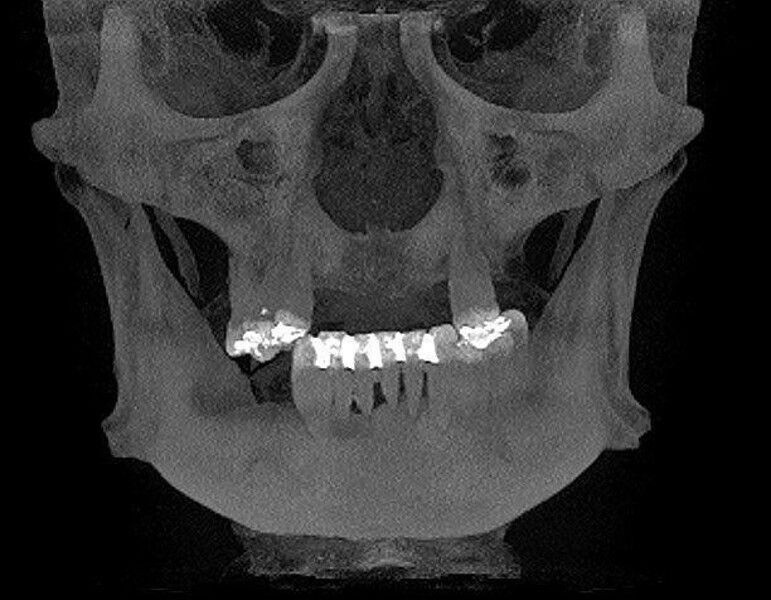

Implantacja z wykorzystaniem szablonu nawigacyjnego 3D